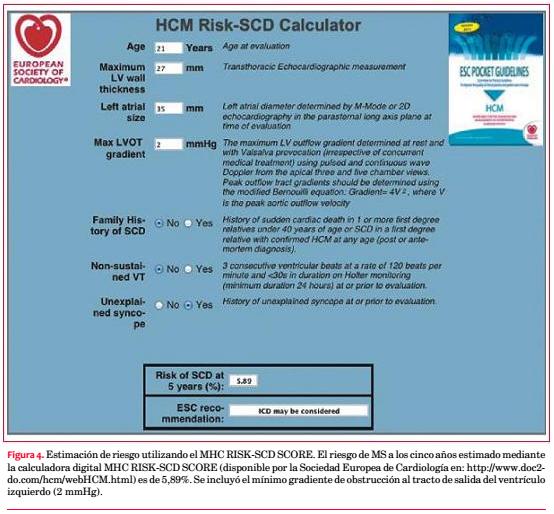

El enfoque terapéutico de la MCH se focaliza en dos grandes objetivos: tratar los síntomas y prevenir la MS. Este último punto obliga a estratificar precozmente el riesgo individual de MS en todos y cada uno los casos. Tradicionalmente, los factores de alto riesgo incluían el grosor parietal máximo >30 mm, la taquicardia ventricular no sostenida, el síncope de causa no aclarada, los antecedentes familiares de MS y la respuesta hipotensora al esfuerzo(1,2). La disponibilidad de algunos scores de riesgo representa un aporte novedoso y de potencial utilidad práctica en la estratificación temprana de la MCH. Estos scores son fácilmente accesibles al lado del paciente, están disponibles en dispositivos portátiles y tienen en cuenta varios factores de riesgo que son integrados como variables continuas y no dicotómicas, lo cual podría graduar mejor su peso individual. Dentro de estos scores destaca el MHC RISK-SCD , un modelo de predicción validado por O’Mahony y colaboradores en un gran estudio de cohortes retrospectivo(18). Esta herramienta permite estimar individualmente el riesgo de MS a cinco años basado en los marcadores tradicionales y en otras variables hasta ahora no consideradas como el gradiente de obstrucción al tracto de salida del VI, las dimensiones de la aurícula izquierda y la edad. El puntaje obtenido por el score estratifica el riesgo individual de MS en tres categorías: bajo (riesgo de MS a los cinco años <4%), moderado (4%-6%) y alto (> 6%). Su uso ha demostrado mejores beneficios en aquellos pacientes con uno o más factores de riesgo clásicos, disminuyendo la tasa de implantes de cardiodesfibrilador automático (DAI) innecesarios, pero mantiene un bajo poder predictivo en la subpoblación de pacientes sin ningún factor de riesgo clásico, en quienes se observa el 30% de las MS. Sin embargo, el MHC RISK-SCD SCORE aún no ha sido validado en pacientes menores de 16 años, deportistas de elite, pacientes sometidos a miectomía ventricular/ablación septal con alcohol o con enfermedades metabólicas infiltrativas. Con base en sus resultados, la más reciente recomendación de la ESC define una indicación de implante de DAI, Clase IIa, nivel de evidencia B, en los pacientes de riesgo elevado(1). En este caso, el MHC RISK-SCD al diagnóstico predijo un riesgo moderado de MS a los cinco años (5,89%), aunque muy cercano al riesgo elevado (figura 4). Razonando con base en los marcadores pronósticos tradicionales(1,2), el riesgo de MS está marcado principalmente por la presencia de síncope de causa no aclarada en un sujeto joven. En este contexto clínico, las guías de la Asociación Americana de Cardiología (2011) señalan que el implante de DAI representaría una alternativa “razonable”(19). En este caso se procedió al implante tras adicionar el riesgo asociado a la edad temprana y la fragmentación del QRS al peso pronóstico moderado (cercano a elevado) sugerido por el score MHC RISK- SCD.Tanto la detección de factores de riesgo adicionales como los aportes pronósticos diferenciales de los nuevos scores versus la consideración exclusiva de los marcadores más tradicionales merecen ser evaluados mediante estudios prospectivos.

Reportamos el caso de un joven con MCH asimétrica anteroseptal que se presentó con síncope y marcadas alteraciones en el ECG, entre las que destaca la fragmentación del complejo QRS, un hallazgo asociado a la presencia de fibrosis miocárdica de potencial valor pronóstico. Estratificamos precozmente el riesgo de MS como moderado, con base en las recomendaciones internacionales y el MHC RISK-SCD SCORE. En este contexto clínico, decidimos proceder al implante de un DAI como medida de prevención primaria razonable. Aun disponiendo de modernas técnicas de imagen y nuevos scores de riesgo confiables al lado del paciente, el perfil evolutivo impredecible de la MCH a menudo dificulta la toma de decisiones terapéuticas.